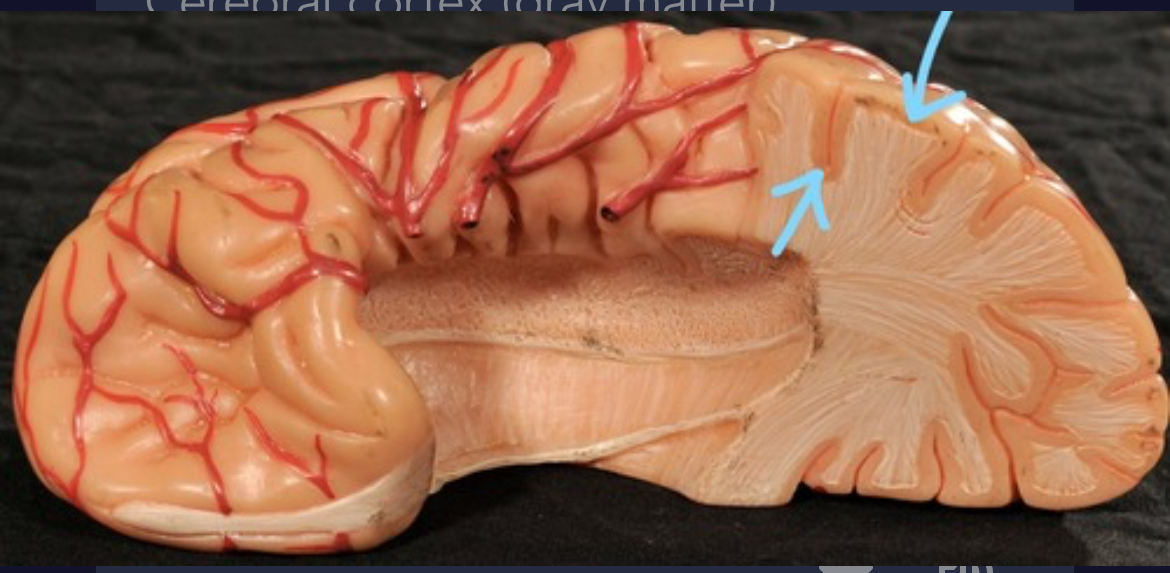

Cerebral cortex (gray matter)

Cerebral medulla (white matter)

Corpus callosum